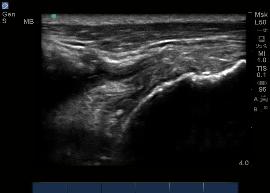

POST-OPERATIVE ROTATOR CUFF: INTACT